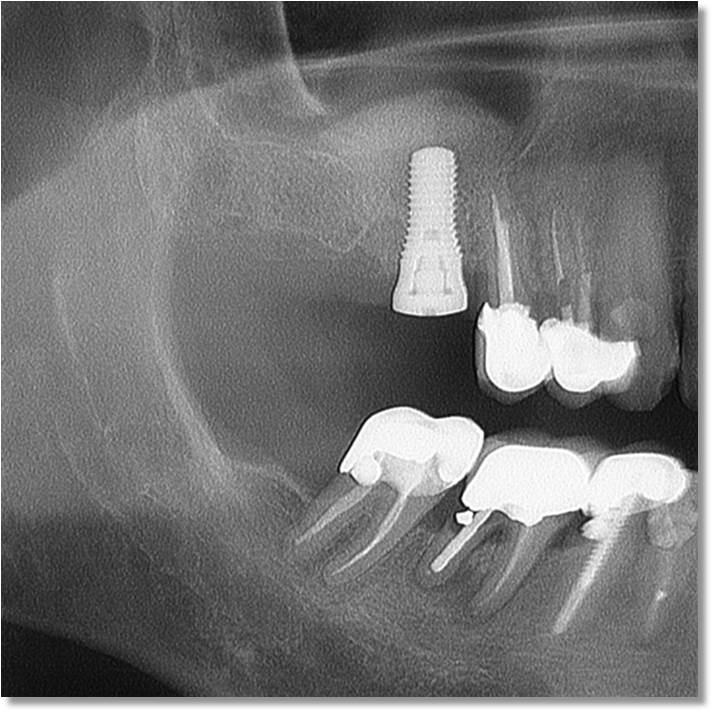

Questa tecnica viene utilizzata dagli anni '80 e si è sempre più imposta nello sport e nella vita quotidiana. Solo recentemente Cavallini e Leghissa hanno pensato di applicarla al post chirurgico odontoiatrico osservando risultati davvero incoraggianti.